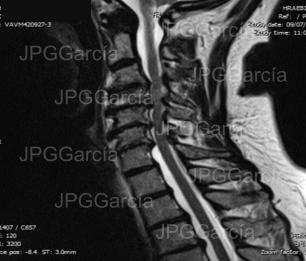

Estudio de resonancia magnética postquirúrgico